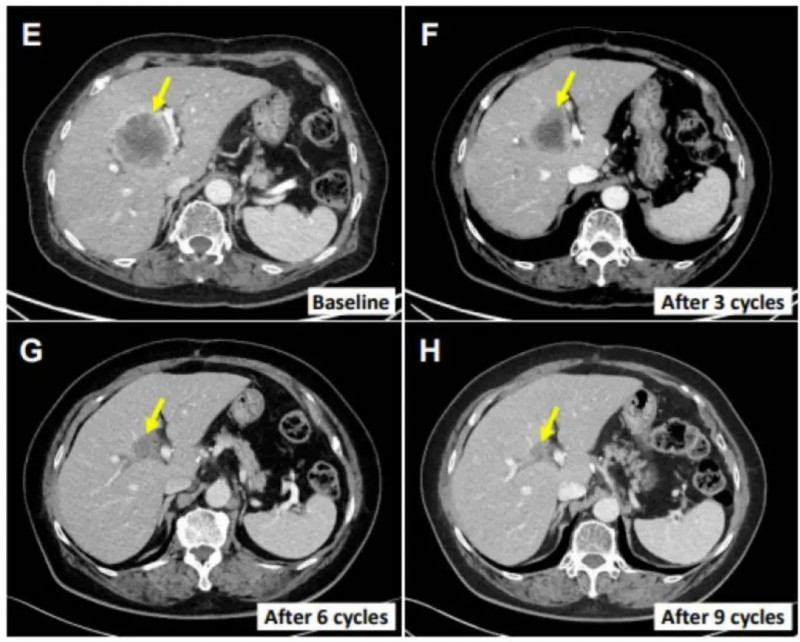

值得一提的是,76岁的肝外胆管癌女性患者(E0217)展现了显著且持久的疗效。该患者既往接受过胆总管节段切除术与胆囊切除术,术后4个月即出现多处肝转移;随后接受吉西他滨联合顺铂全身化疗,但疗效不佳,肝脏病变持续进展。入组接受SMT-NK联合帕博利珠单抗治疗后,其肝转移病变大幅减少70.4%(详见下图E-H),且在初始治疗后12个月仍保持无进展状态。

▲图源“Cancers (Basel)”,版权归原作者所有,如无意中侵犯了知识产权,请联系我们删除